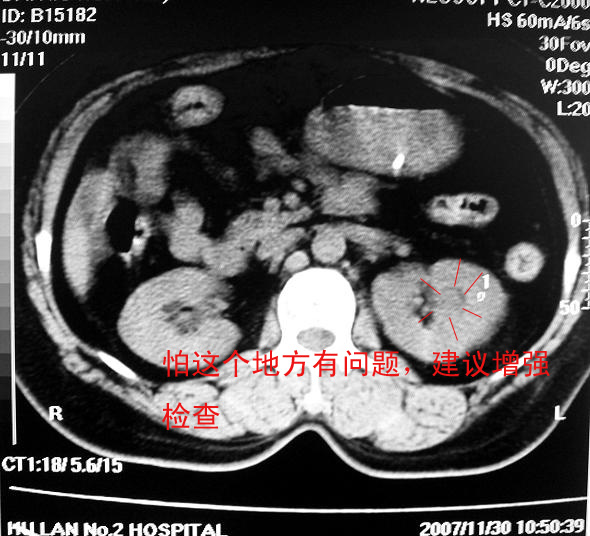

标题: CT10687:肾脏CT,请会诊

女,53岁,尿频尿急来诊,其他层面无异常未上传。

肾柱肥大可能?请增强结合b超

像是一个正常的驼峰样改变!!不放心就做个增强

应该是正常的表现!左肾上极外侧变异较多;建议增强!

正常!日常检查中多有肾驼峰状改变,为正常变异